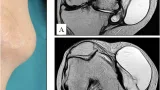

昨日大腿骨転子部骨折に対する手術を行った後期高齢患者さんの状態を確認するために, 9時に出勤.